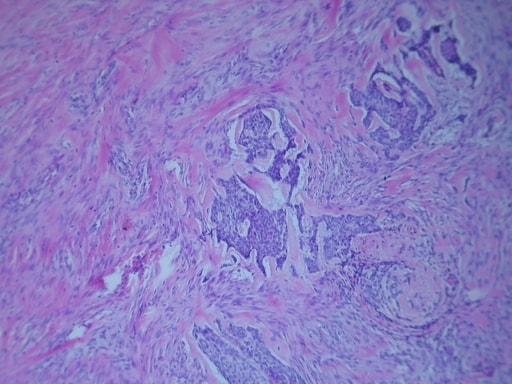

CARCINOMA MUCOCUTÁNEO